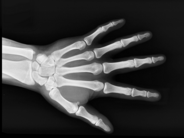

En los últimos años, la institución del Síndic de Greuges ha recibido varias quejas relacionadas con las pruebas óseas que se practican a los jóvenes migrantes para determinar su edad. En el informe La situación de los niños migrantes sin referentes familiares en Cataluña, de 2018, la institución ya denunció que estas pruebas presentaban carencias desde el punto de vista de las garantías jurídicas y médicas.

Hace un tiempo la institución tuvo conocimiento de que jóvenes migrantes que residen en centros de acogida o de emergencia y que tienen pasaporte o documentación que acredita que son menores de edad están a la espera de que la Fiscalía les practique esta prueba de edad. En función del resultado que se obtenga, se detiene su proceso de protección e inserción, lo que hace que a menudo acaben en la calle. Sin embargo, la institución no tiene constancia de ningún proceso de invalidación de la documentación que aportan los jóvenes.

En este sentido, existe doctrina jurisprudencial del Tribunal Supremo que indica que el inmigrante con pasaporte o documento equivalente que demuestre que es menor de edad no puede considerarse extranjero indocumentado ni ser sometido a pruebas para determinar su edad. Y, en caso de que el documento no se considere fiable, es necesario hacer un juicio de proporcionalidad y ponderar adecuadamente las razones que justifican que sea necesario practicar este tipo de pruebas.

En cualquier caso, las técnicas médicas, especialmente si son invasivas, no pueden aplicarse indiscriminadamente para determinar la edad en estos casos.